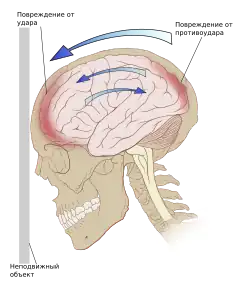

- Ушиб головного мозга: лёгкой, средней и тяжёлой степени (клинически). Ушиб головного мозга проявляется в ушибленной ране ткани мозга. Ушиб удар-противоудар наносится когда мозг ударяется о стенку черепа в месте непосредственного воздействия внешнего объекта на голову, получает одну ушибленную рану и затем ушибленная рана наносится на противоположную сторону мозга при резком замедлении движения ткани мозга. Клинические проявления зависят от расположения ушиба, и включают изменение психического состояния, повышенную сонливость, спутанность сознания, тревожное возбуждение. Небольшие интрапаренхиматозные кровоизлияния и припухлость окружающей ткани часто можно определить при компьютерной томографии.